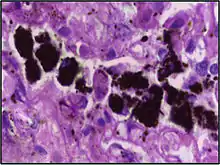

Alveolar macrophages are frequently seen to contain granules of exogenous material such as particulate carbon that they have picked up from respiratory surfaces. Such black granules may be especially common in smoker's lungs or long-term city dwellers.

Comparison of pigmented pulmonary macrophages

| Disease | Macrophage name | Macrophage pigment appearance (HE stain) | Usual macrophage location | Associated medical history | Image | Image comment |

| Anthracosis | Black-brown granules | Interstitium (perivascular) | ![]() |

Black arrow shows interstitial anthracotic pigment. Nearby macrophages (white arrow) can be presumed to contain anthracotic pigment. | ||

| Respiratory bronchiolitis | "Smoker’s macrophages" | Yellow to light brown and finely granular[4] | Airways (especially respiratory bronchioles) | Tobacco smoking | ![]() |

Smoker's macrophage in center |

| Chronic pulmonary congestion | Siderophages | Brown-golden and refractile.[5] | Alveoli[6] |

|

![]() |

Siderophage (black arrow), and interstitium with edema, hemosiderin deposition (black arrow) and collagenous thickening, indicating heart failure. |